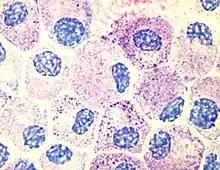

- A resident cell of connective tissue that contains many granules rich in histamine and heparin.